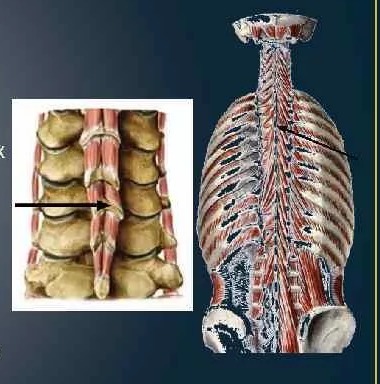

2. Поперечно-остистая мышца,составляющая средний слой. Крепится к поперечным и остистым отросткам позвонков,состоит из нескольких пучков,которые совместно тянутся по всей длине позвоночника,выполняет ту же функцию разгибания позвоночника и его вращения.

3. Межостистые мышцы,самый глубокий слой. Расположены между остистыми отростками соседних позвонков почти по всей длине позвоночника,кроме крестца и копчика. Функции всё те же -- разгибание и удерживание позвоночника.

(Картинки даны последовательно)